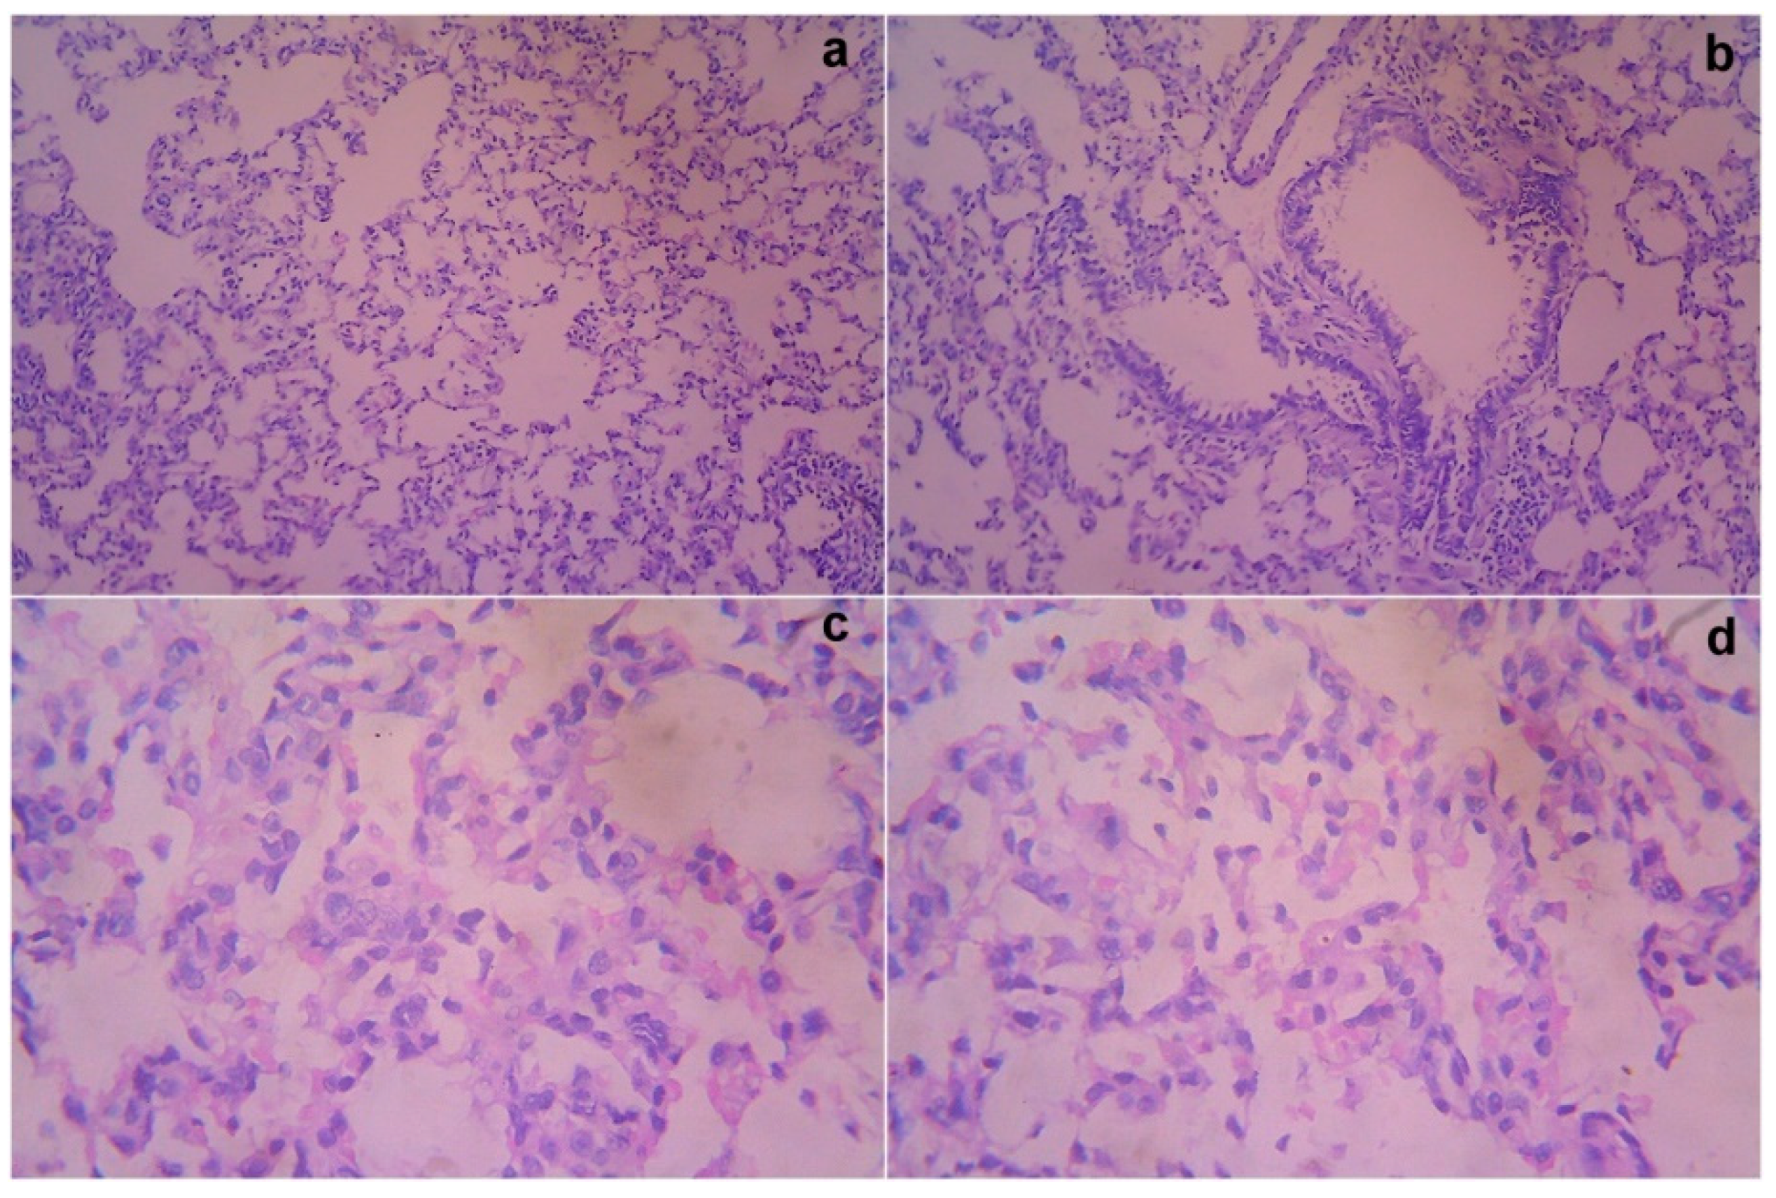

2.8. Histopathological Studies

3.6. Necropsy and Histopathology

3.7. Acute Toxicity and Safety Study